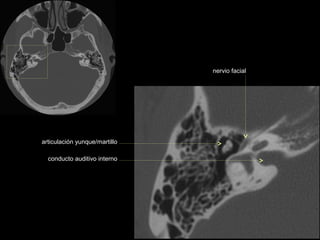

nervio facial

articulación yunque/martillo

conducto auditivo interno